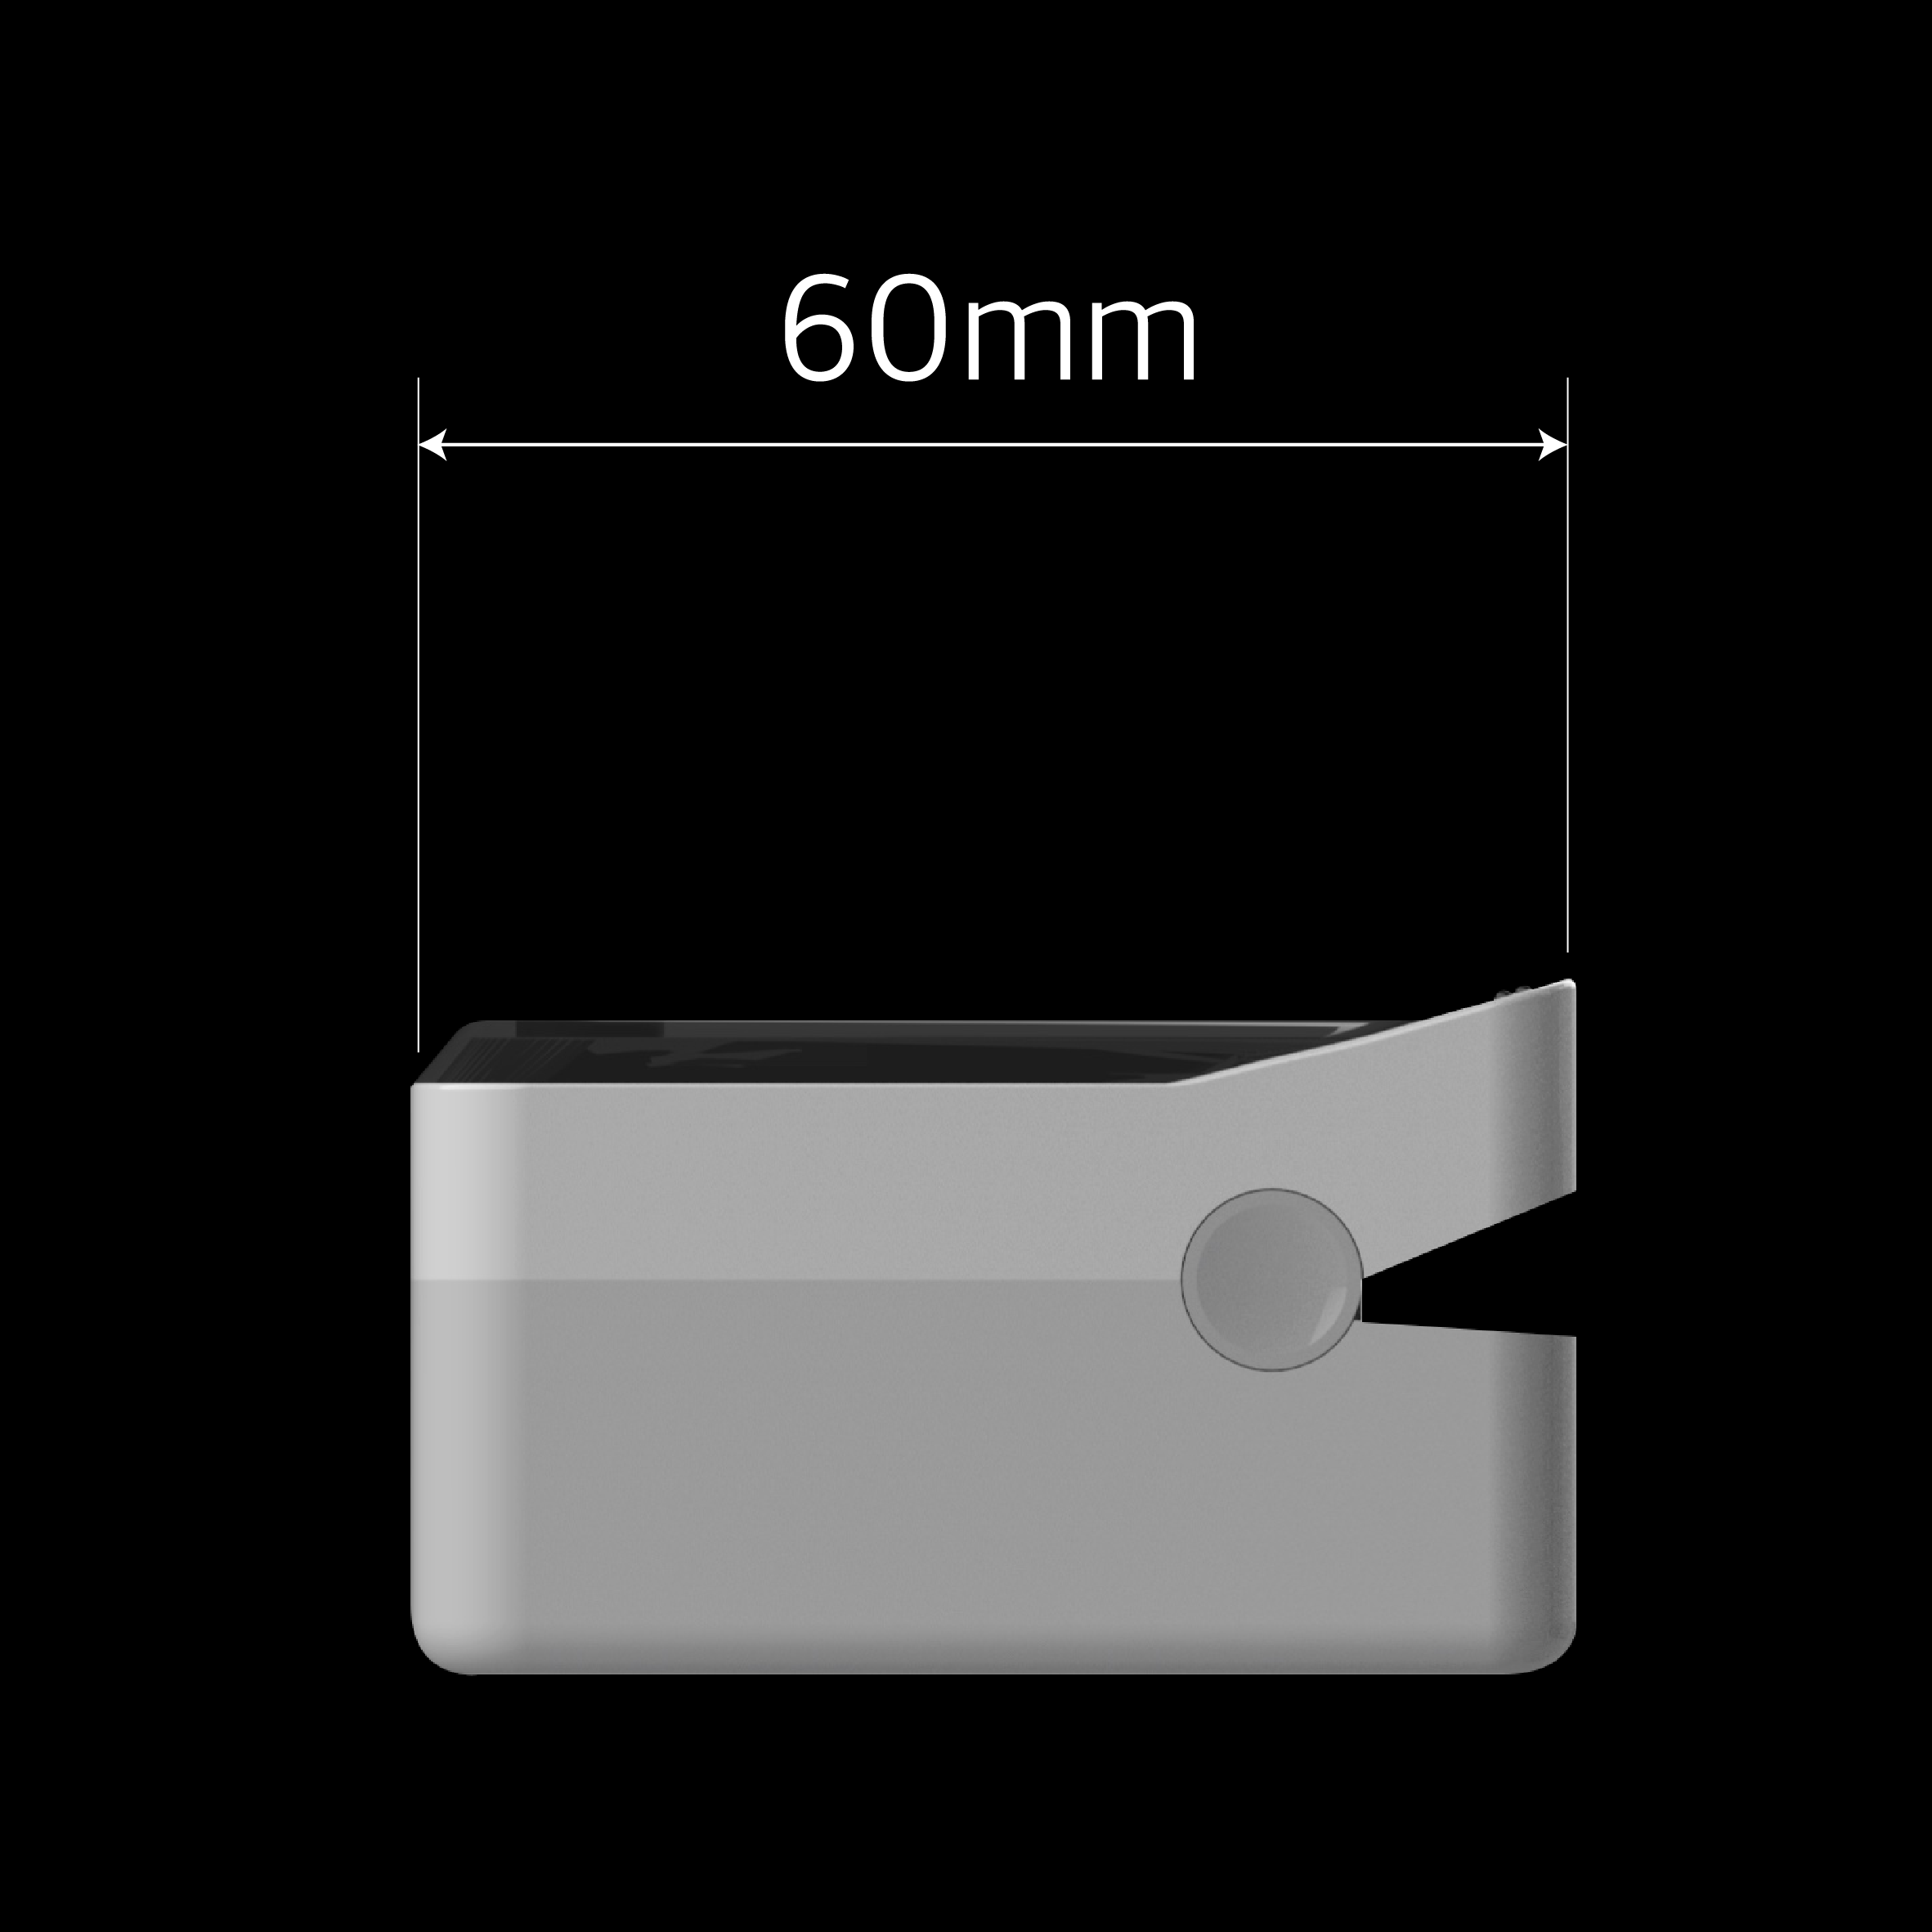

AI의료로봇

AI의료로봇

(가정+병원)가정이나 병원에서 사용할 수 있는 비침습 ai

혈당측정장치를 개발하여 누구나 쉽게 혈당을

측정할 수 있는 새로운 방법을 제시합니다.